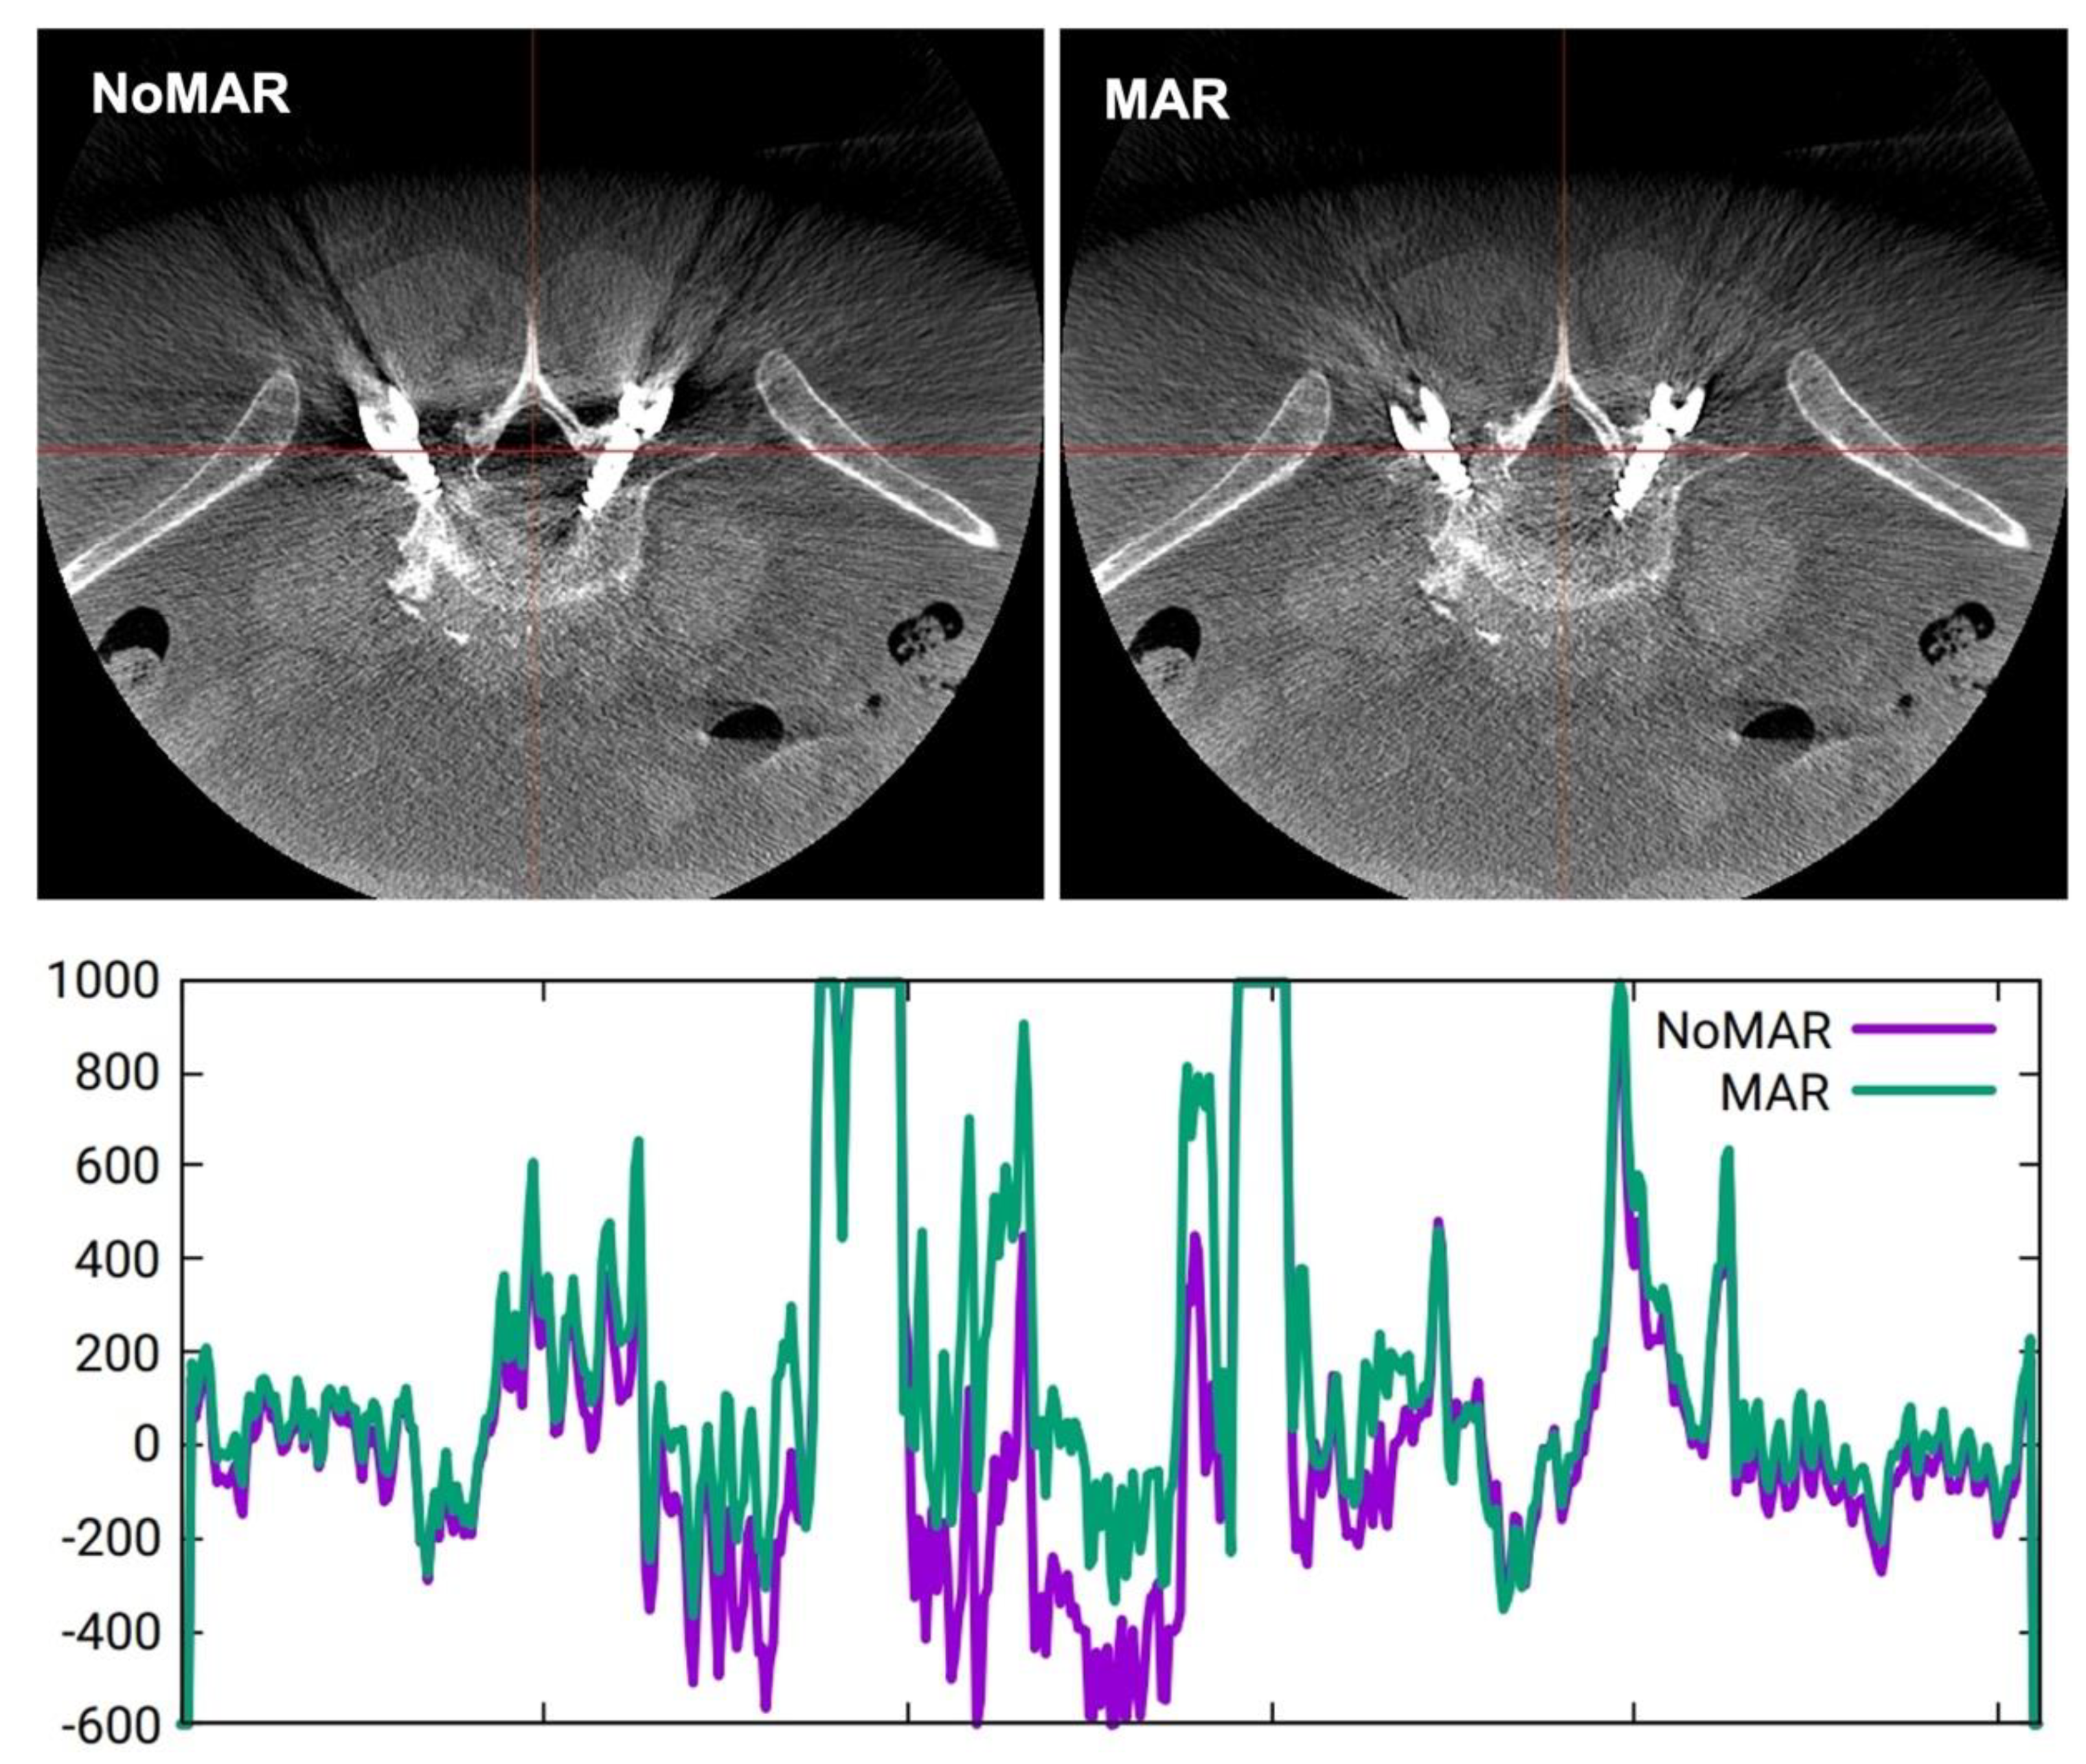

Figure 2.

Variation of Hounsfield units across a coronal plane section (red line) comparing NoMAR (purple curve) and MAR (green curve).